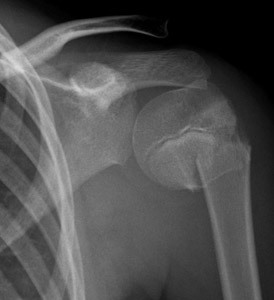

What are the indications for treatment of a pediatric proxiaml humerus fracture?

Acceptable alignment of a humeral shaft fracture